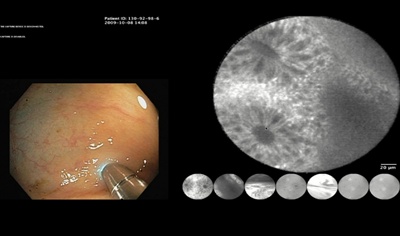

A probe-based confocal laser endomicroscope developed by the venture-backed French company Mauna Kea Technologies has shown strong clinical potential to diagnose a wide range of serious diseases including cancer, according to a raft of new studies just published.

No fewer than five clinical and pre-clinical studies appearing in leading medical journals over the past month have highlighted how Mauna Kea’s “Cellvizio” probe can help physicians confirm or rule out the presence of various forms of early-stage cancer or pre-cancerous tissue, as well as diagnosing urinary tract diseases and estimating the severity of asthma.

Founded by its CEO Sacha Loiseau in 2000, Mauna Kea received FDA and CE Mark approval for the Cellvizio probe in 2005, and it has now been used in nearly 200 hospitals and medical research centers around the world. The probe features miniaturized optics, optical fiber bundles and advanced image processing to combine some of the key features of a confocal microscope within an endoscope form.

One of those features is the ability to observe “slices” of tissue within the body – just as would be done physically after a regular biopsy is taken from a patient. Mauna Kea has developed various forms of confocal probes for different medical applications – including versions for observing the colon and the respiratory tract. The standard probe’s lateral resolution is 3.5 µm, and a magnification of 1000x is possible for observing mucosal tissue.